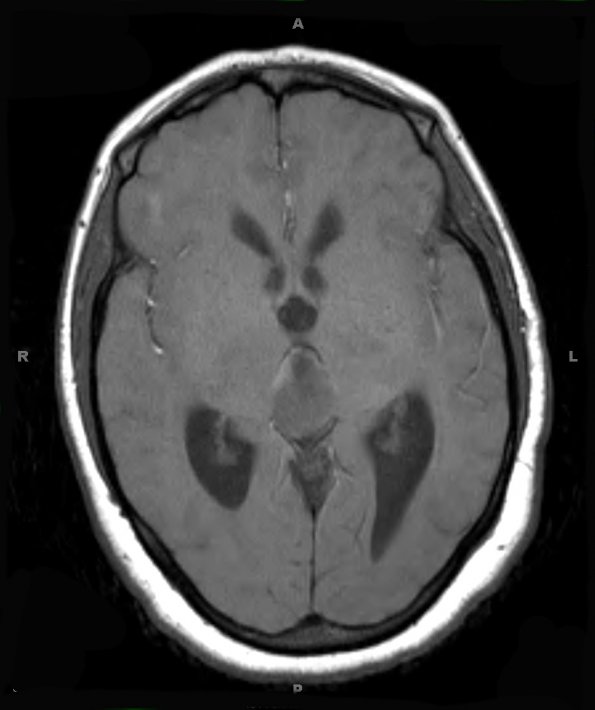

Washington University Experience | NEOPLASMS (PINEAL) | PPTID (Pineal Parenchymal Tumor Intermediate Differentiation) | 3A2 PPTID (Case 3) T1 2

3A2,3 The tumor is isointense in T1-weighted image (3A2) and enhances with contrast (3A3).